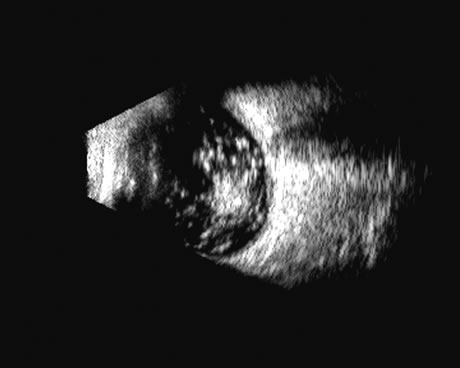

Fig. 2. Ciliary body retroiridal cyst can be demonstrated in this occult area as clear, usually rounded, single or multiple cystic spaces. They are nearly always clear acoustically and may at times contact the lens and occasionally cause cataract formation.

Fig. 3. Solid tumor of the ciliary body, often appearing relatively round, but occasionally irregularly shaped to match the area of the ciliary body itself. It can be presented in 3D for measurement of growth, but usually these highly lethal tumors are treated soon after presentation.